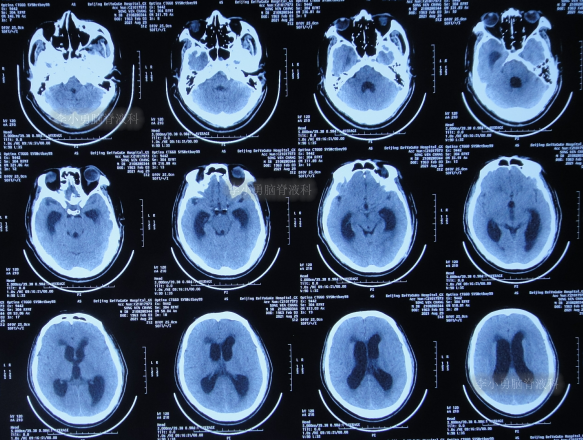

2021年8月28日(第1家医院第3次治疗12天后),出现脑积水(图-2)。

图-2:2021年8月28日头颅CT